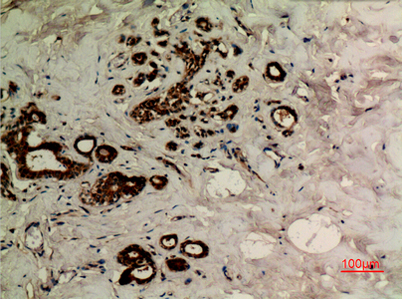

Tubulin α (Acetyl Lys40) rabbit pAb

Product name: Tubulin α (Acetyl Lys40) rabbit pAb

Dilutions: Western Blot: 1/500 - 1/2000. IHC-p: 1:100-300 ELISA: 1/20000. Not yet tested in other applications.

Immunogen: The antiserum was produced against synthesized Acetyl-peptide derived from human TUBA1A around the Acetylation site of Lys40. AA range:1-50

Cellular localization: Cytoplasm, cytoskeleton.